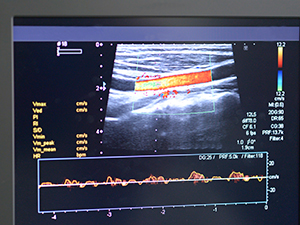

La Angioresonancia magnética (ARM) es el estudio de los vasos sanguíneos mediante el uso de la resonancia magnética. Se trata de un técnica no invasiva, a diferencia de la angiografía habitual, durante la cual se ha de introducir un catéter dentro del sistema sanguíneo del paciente para poder observar la estructura de los vasos y sus posibles alteraciones. La resonancia magnética es una prueba de imagen que se basa en someter al paciente a un campo magnético y unas ondas de radiofrecuencia que estimulan los protones del organismo y, tras su estimulación, estos devuelven una señal que es recogida por un ordenador que la transforma en imágenes en dos o tres dimensiones de las estructuras analizadas.